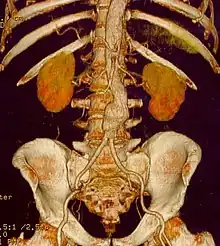

Abdominal aortic aneurysm

Abdominal aortic aneurysms (AAAs) are more common than their thoracic counterpart. One reason for this is that elastin, the principal load-bearing protein present in the wall of the aorta, is reduced in the abdominal aorta as compared to the thoracic aorta. Another is that the abdominal aorta does not possess vasa vasorum, the nutrient-supplying blood vessels within the wall of the aorta. Most AAA are true aneurysms that involve all three layers (tunica intima, tunica media and tunica adventitia). The prevalence of AAAs increases with age, with an average age of 65–70 at the time of diagnosis. AAAs have been attributed to atherosclerosis, though other factors are involved in their formation.[7]

The diagnosis of an abdominal aortic aneurysm can be confirmed by the use of ultrasound. Rupture may be indicated by the presence of free fluid in the abdomen. A contrast-enhanced abdominal CT scan is the best test to diagnose an AAA and guide treatment options.[10]

For abdominal aneurysms, the current treatment guidelines for abdominal aortic aneurysms suggest elective surgical repair when the diameter of the aneurysm is greater than 5 cm (2 in). However, recent data on patients aged 60–76 suggest medical management for abdominal aneurysms with a diameter of less than 5.5 cm (2 in).[19]

Endovascular treatment of aortic aneurysms is a minimally invasive alternative to open surgery repair. It involves the placement of an endo-vascular stent through small incisions at the top of each leg into the aorta.